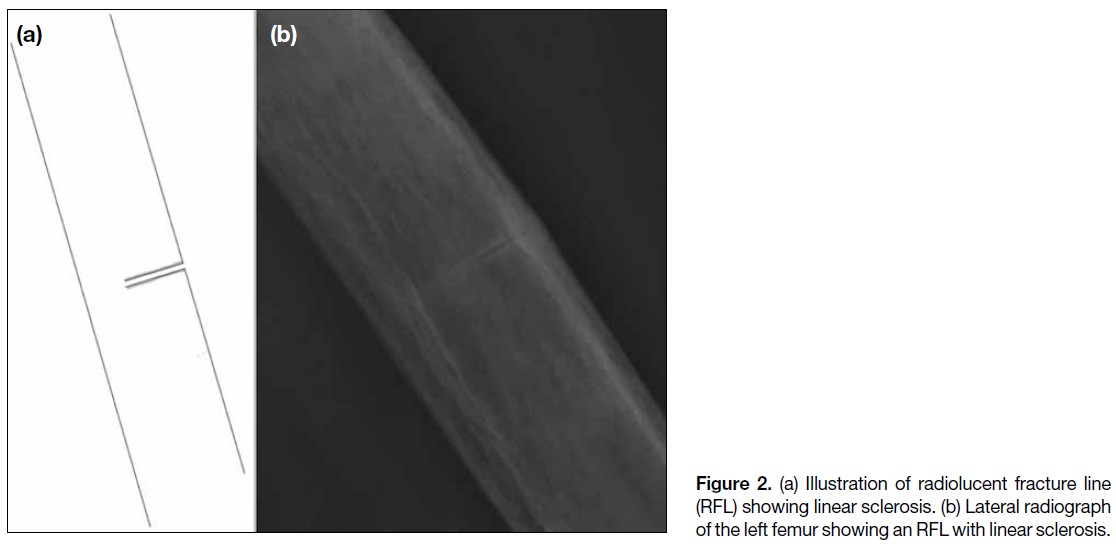

clinical orthopaedic experience. RFLs were categorised

into one of four patterns: (1) RFL without sclerosis

(Figure 1); (2) RFL with linear sclerosis (Figure 2);

(3) RFL with patchy continuous sclerosis (Figure 3); and

(4) RFL with patchy non-continuous sclerosis (Figure 4).

Figure 2. (a) Illustration of radiolucent fracture line

(RFL) showing linear sclerosis. (b) Lateral radiograph

of the left femur showing an RFL with linear sclerosis.